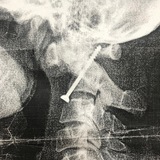

Вертебропластика

🧠Что такое вертебропластика?

✅Вертебропластика - это малоинвазивная (без разреза, через прокол) операция, когда в позвонок по игле вводится специальный цемент, который укрепляет позвонок.

❓Когда это делается?

при переломах позвонков

при наличии в позвонке гемангиомы (сосудистого образования, которое снижает прочность позвонка)

💉Какие плюсы?

полуамбулаторная процедура (1-2 дня в стационаре)

без общего наркоза с интубацией (местная анестезия, плюс седация)

без разреза, через прокол

⚠️У вас есть вопросы про вертебропластику? Пишите, с удовольствием отвечу.